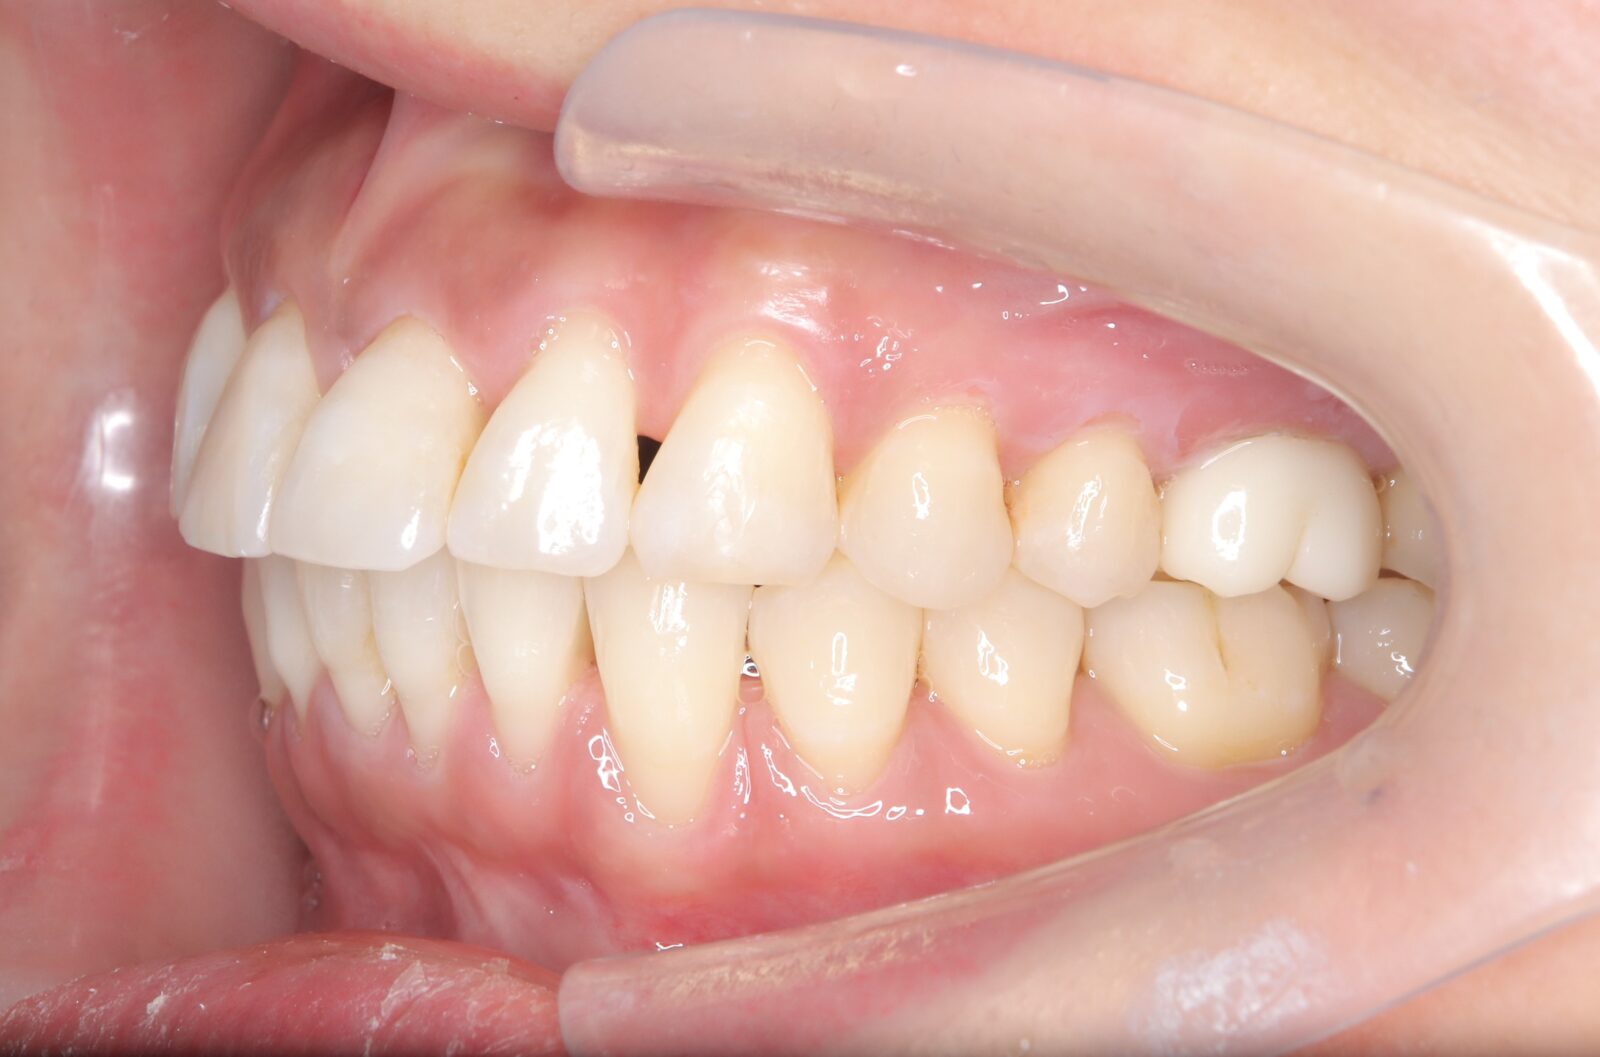

インビザライン(全体矯正)+ホワイトニングコースの症例

上下の前歯の歪みと奥歯のすれ違いをインビザライン(全体矯正)とホワイトニングで綺麗に矯正。

・費用:935,000円(税込)

・治療期間:30ヶ月

・通院回数:30回

・31歳女性

-リスクと副作用-

・長時間マウスピースを装着するため、むし歯や歯周病のリスクがある。治療後はリテーナーを装着しないと後戻りしてしまうリスクがある。

・ホワイトニング剤の影響で知覚過敏が起こる可能性がある。色が徐々に戻る可能性がる。